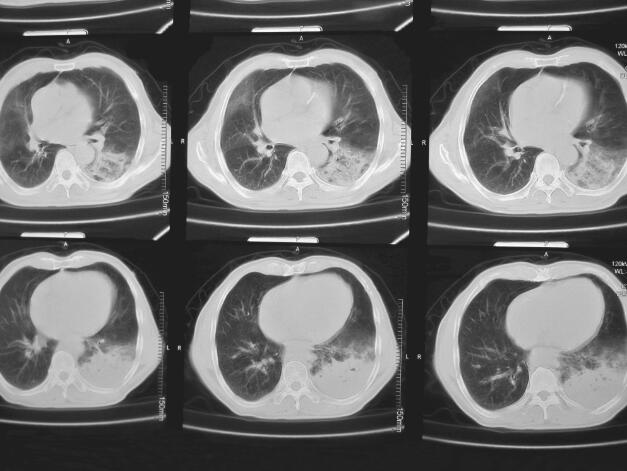

患者,刘某,男,66岁。因“反复咳嗽、咳痰2年余,再发加重3天”于2014年3月7日入院。自2012年以来,患者无明显诱因出现反复咳嗽、咳痰,多为白色泡沫痰,咳嗽剧烈时伴胸闷、气喘不适,间断高热,多次在外院住院治疗,每经抗感染及止咳祛痰等对症治疗后病情可缓解,出院后患者咳嗽、咳痰症状仍反复。自2012年起病以来,患者多次行肺部CT(图1~图4)检查提示“左下肺大片状及右上叶片状阴影”,行抗感染治疗后右肺上叶稍吸收,左下肺片状影吸收欠佳。2013年8月考虑患者“肺结核”不能排除,在本市结核病医院,查T-spot(+),后给予三联抗结核(异烟肼+利福平+乙胺丁醇)治疗2个月,咳嗽、咳痰未见明显好转。2013年11月曾因咳嗽、咳痰加重入我科,给予抗感染(左氧氟沙星)及继续抗结核(异烟肼+利福平+乙胺丁醇)治疗,期间患者因大便潜血(+)行肠镜检查,提示“乙状结肠直肠新生物”,病理检查示“乙状结肠腺癌”,于2013年12月8日转普外科行“乙状结肠癌根治术”。此次入院前3天,患者受凉后再发咳嗽,咳白色泡沫痰,量较多,偶为粉红色泡沫痰,咳嗽剧烈时感憋气、胸痛,无畏寒、发热,无恶心、呕吐,无双下肢水肿等不适。

图4 2013年12月17日肺部CT